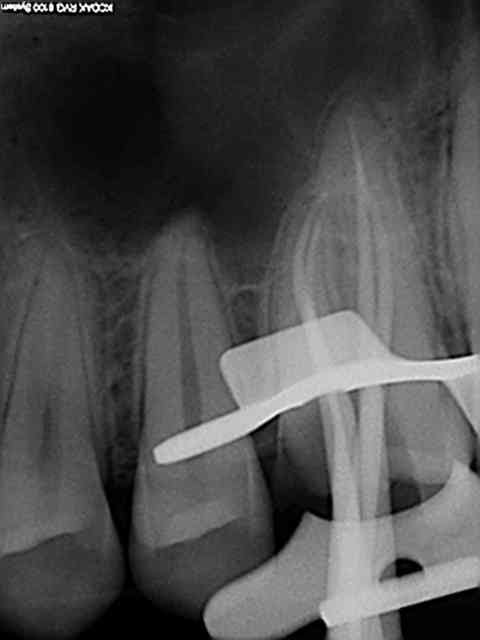

Ce sont des cones dentsply mais pas les réciprocs. je les scelle au tubuli seal en pompant un peu ( d'ailleurs sur la 25 ci dessous qui avait un 4eme ca a fait un dépassement preuve que ca fuse) je les coupe ensuite au système B avec le pluggeur qui sert à faire le bouchon apical.

Tres pratique d'ailleurs pour faire le cas échéant les tenons dans la séance de l'endo, l'empreinte et la provisoire dans la foulée.

R1 yd7c5a - Eugenol

R2 rn8qyd - Eugenol

R2 ts2qmh - Eugenol

Tu as fait des progrès. Disons par exemple que sur la deuxième prémolaire, tu es allé un poil trop loin, ce qui a réduit sérieusement la constriction apicale. Peut être que que tu mesures ta LT un demi millimètre plus longue que nécessaire.